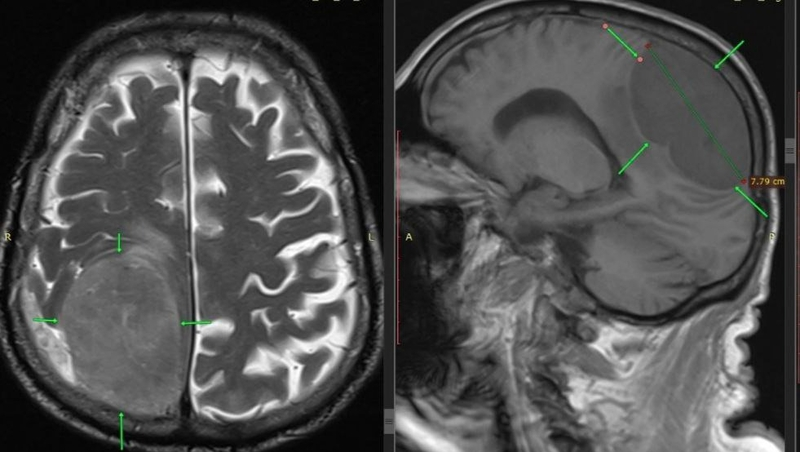

«Операция прошла успешно. На контрольной томографии мозга признаков кровотечения в ложе удалённой опухоли не было, мозг расправился, восстановились нормальные размеры и форма желудочковой системы»,

— рассказал нейрохирург Вадим Зотов.